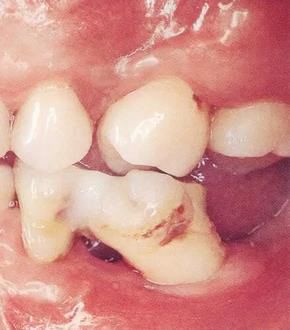

▲圖2

牙位異常例②。牙體傾斜。

【牙位異?!坑绊懙窖乐芙M織的牙位異常

▲圖3

牙位異常例③。邊緣嵴高度不整齊。